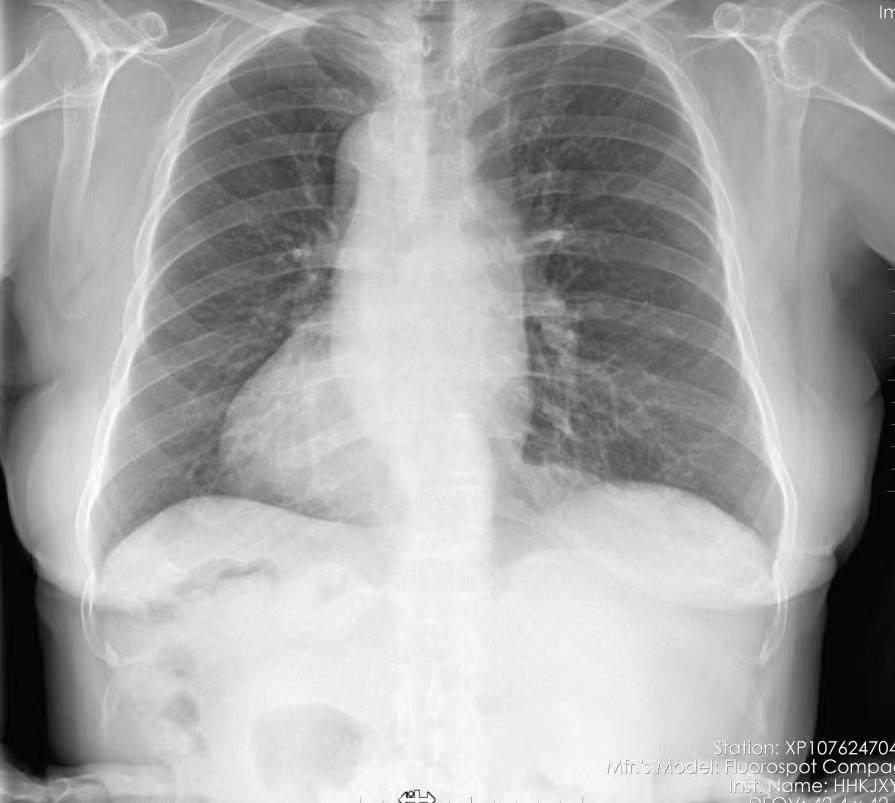

“镜面人”又称全内脏反位,即心脏、肝脏、脾脏、胆等器官的位置与正常人相反,犹如镜中影像。据文献报道,镜像右位心发生率约为万分之二。

原来,杨女士的心脏长“反”了,心脏彩超显示患者镜像右位心,即患者的心脏位于胸腔的右侧。由于解剖结构和空间构象特殊,结构的反向使手术手法、器械使用方向和平时完全不一样,手术思维及操作均反向。为此类“镜面人”做手术,要一心两用,时刻提醒自己这一情况。于是,杨女士慕名来到郑州市第七人民医院,该院心内八病区主任孙俊华详细了解患者病情,并邀请全国知名冠脉专家西京医院的胡涛教授,与心内科介入团队进行了充分的术前评估,针对手术中可能遇到的问题制定了周密完善的手术方案及应急预案,后经7个小时手术,前向血流恢复,手术成功。

孙俊华介绍,为右位心患者实施手术,手术操作难度大,因常规的操作器械均是为正常心脏位置的患者设计,所以为右位心患者实施手术时,有可能会出现导管难以到位等困难。左冠状动脉起源于正常右冠状动脉窦,右冠状动脉起源于正常左冠状动脉窦,右位心及冠状动脉的异常起源,导致冠状动脉造影操作困难,对于手术医生来说难度极高,要求术者必须有过硬的基本功和扎实的理论基础,还要对心脏的解剖结构和影像检查有较好的掌握。

冠状动脉粥样硬化性心脏病(CTO)是冠脉介入治疗的难点,右位心已经罕见,而右位心CTO更罕见,目前世界上尚未有数据报道右位心CTO介入治疗报道。孙俊华提醒,若发现有“右位心”,还需尽早确诊右位心类型,以及体内心血管畸形和其他内脏转位的情况,并在就诊时告知医生,有助于避免疾病的误诊,还能有效指导手术路径的选择,以免延误病情。